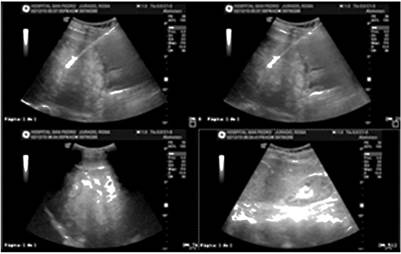

Her complete blood count was normal, her serum C-reactive protein (CRP) level was high (15 mg/dL), and electrolytes, renal function, blood glucose and coagulation times were within normal values. Ultrasound of the liver and bile ducts showed multiple focal lesions of possible metastatic origin (Figure 1).

Figure 1 Ultrasound of the liver and bile ducts showing multiple focal lesions of possible metastatic origin.

When metastasis of melanoma to the digestive tract is suspected, diagnostic images should be taken. The first basic stage of diagnosis is abdominal ultrasound a non-invasive, low-cost exam. Another test is computed tomography, whose sensitivity for identifying melanoma metastases in the digestive tract is only 60% to 70%. In each case, when metastases in the digestive tract are clinically suspected, other tests are necessary when a CT scan is negative. The PET/CT exam has greater sensitivity than CT and should be done if available. 4. In our case, ultrasound and a CT scan revealed metastases in the digestive tract (Figure 1 and 2).